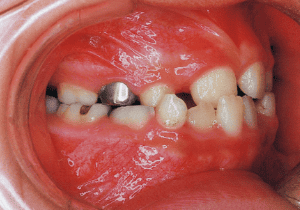

1 At start of treatment 7-21-’88

A case of diverted and cross bite during the deciduous dentition. Despite early treatment, the deviation progressively worsened with age, necessitating surgical treatment. At the initial visit, the patient had a deciduous dentition, and observation was planned (3). With the eruption of the permanent incisors, the mandible shifted slightly to the right, resulting in a cross bite (1) At this point, asymmetry can be confirmed in the front view. However, it is slight. The cephalometric X-ray reveals a structure with a slightly dominant mandible, but asymmetry in the mandibular ramus is not observed.

3 Initial Visit 6-17-’87

4 At start of treatment 7-21-’88